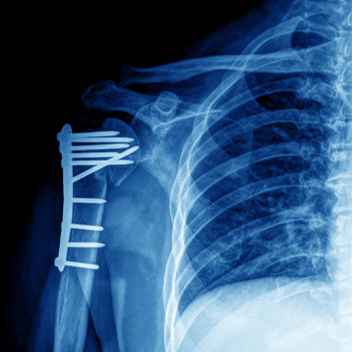

钢板和螺钉固定

A.锁骨骨折, B.前方钢板固定